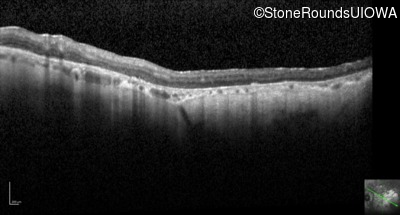

Optical Coherence Tomography - Right - 10/200 sc

Exemplar / OCT Stack